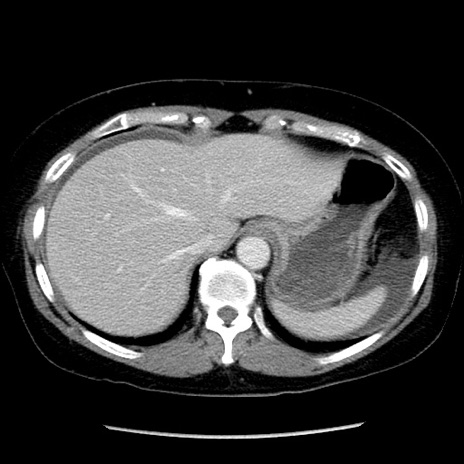

症例6(横断像)

【症例】50歳代女性

【主訴】下腹部痛

【現病歴】本日朝より下痢2回あり。 昼食を食べた後、嘔吐3回、下腹部痛認め、症状軽快せず、当院救急搬送。

最終食事:本日昼(生ものなし)。 昨日の夜、刺身を食ぺたとのこと。周囲に同様の症状の者なし。普段、排便は毎日あるとのこと。

【既往歴】卵巣癌術後(8年前に当院で卵巣摘出)

【身体所見】 意識清明、腹部:平坦、腸蠕動音→、やや硬、下腹部自発痛・圧痛あり、反跳痛あり、筋性防御なし。

【データ】WBC 16000、CRP 0.01